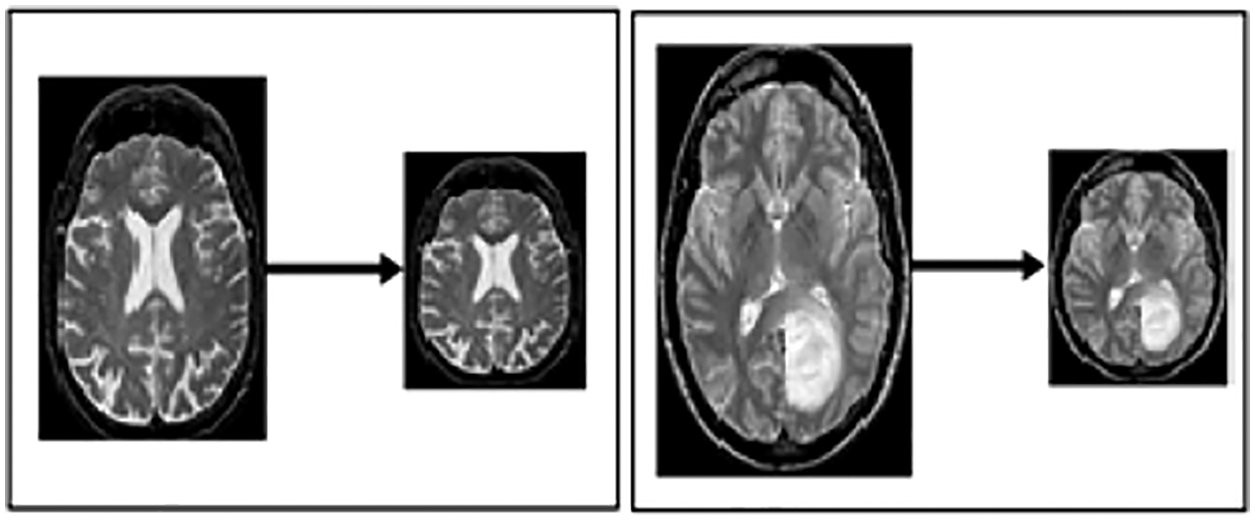

Sliding Window Crop: This approach is used to crop the size of the picture for better classification and segregation. The approach makes it easy to resize the image; it crops the image according to the window size in which it can be kept and fit perfectly by both height and width. In addition, it also makes it easy the process of transfer learning and feature extraction because only the target area of the image will be left for processing. When this procedure is performed, it will be marked as the window size N of the slide size. Then, this will become M(N*N) on the images, equal to 00.05 N. The layers over diverse harvests are utilized to secure the data structure from any kind of damage.

Resizing: This step resizes the image to best fit in window sliding. Fig. 3 illustrates the resized image from one format to another, with the notation of x, y and z, which portrays the resizing value by 224*224.

Figure 3: Resized MRI image